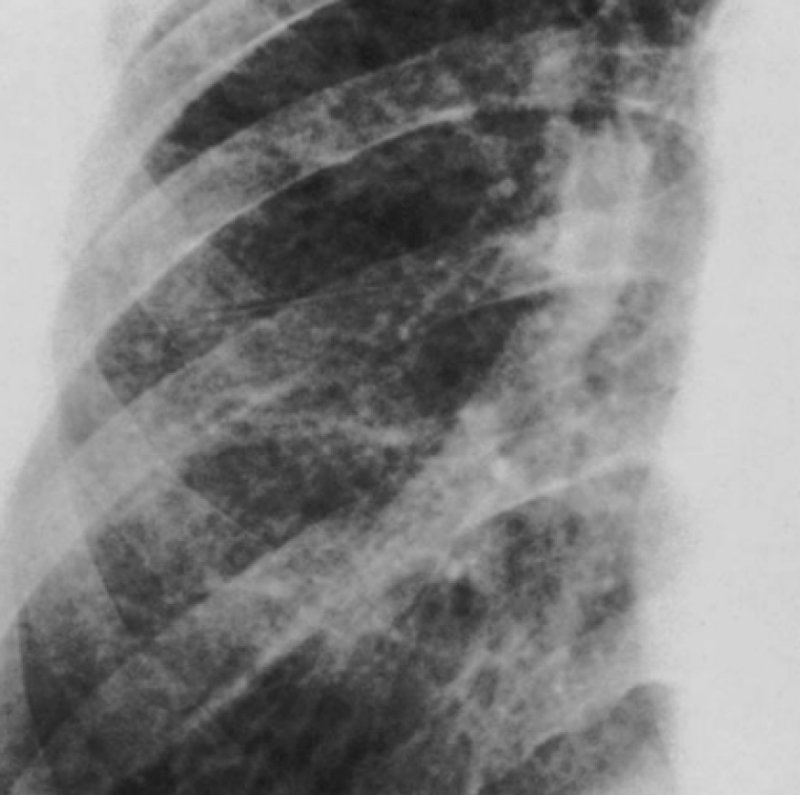

Рисунок 4. Силикоз. Определяются диффузные двусторонние интерстициальные изменения – распространенный пневмосклероз